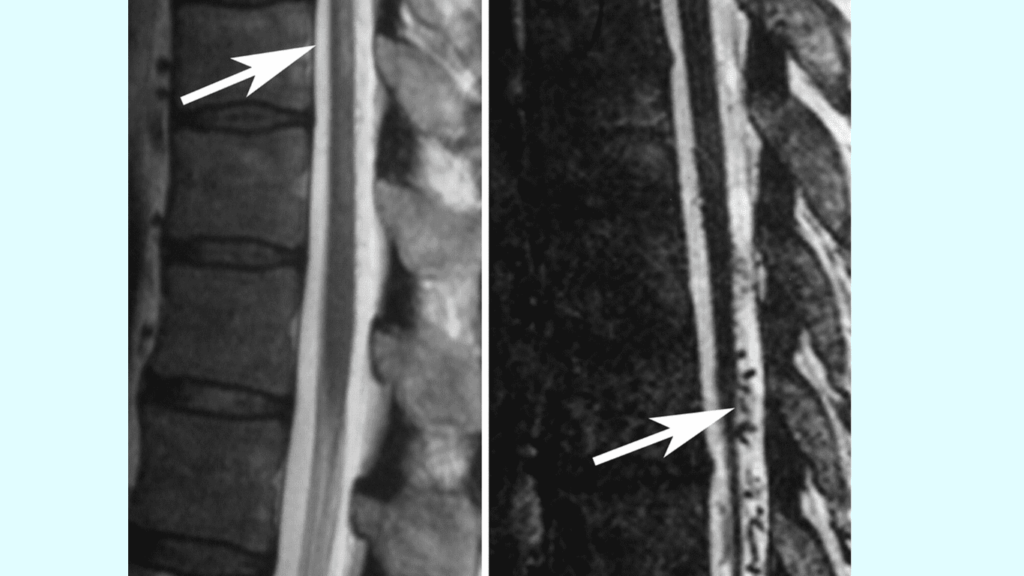

Diagnosing SDAVF can be challenging due to its rarity and varied symptoms. However, healthcare professionals may use a combination of imaging studies, such as magnetic resonance imaging (MRI) and angiography, to identify the abnormal blood flow in the spinal cord. They typically impact older men and are commonly located in the thoracolumbar region. The arteriovenous (AV) shunt is situated within the dura mater near the spinal nerve root, where arterial blood from a radiculomeningeal artery enters a reticular vein. - Risk Factors: